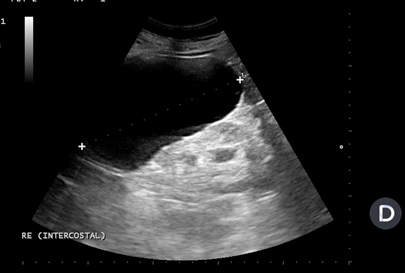

Se realiza ecografía renal a primaria que objectiva una imagen anecoica a nivel de polo superior de riñón izquierdo de 13 x 9 cm que no capta Doppler compatible com un quiste simple renal (Bosniak I).